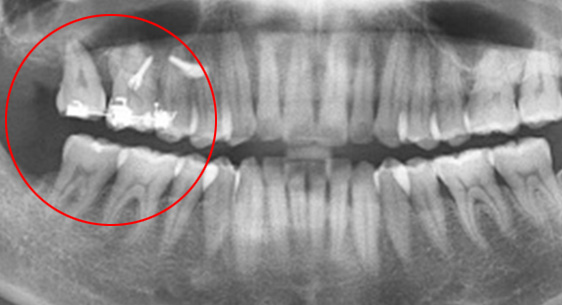

신경관이 막혀 있는 경우 재 신경치료로 낫지 않는 경우, 포스트가 있어 재 신경 치료를 할 수 없는 경우, 치아 뿌리까지 염증이 심하지만 이러한 염증을

제거 할 수 없는 경우, 고운미소 치과에서는 치조골 주위 염증조직을 제거하는 치근단절제술을 시행합니다.

기존 신경치료는 양호한 상태이나 치근부위에 염증과 치조골 소실이 진행 중

치아 뿌리 쪽 잇몸을 절개하고 치조골 부위의 염증조직을 제거. (난이도 중)